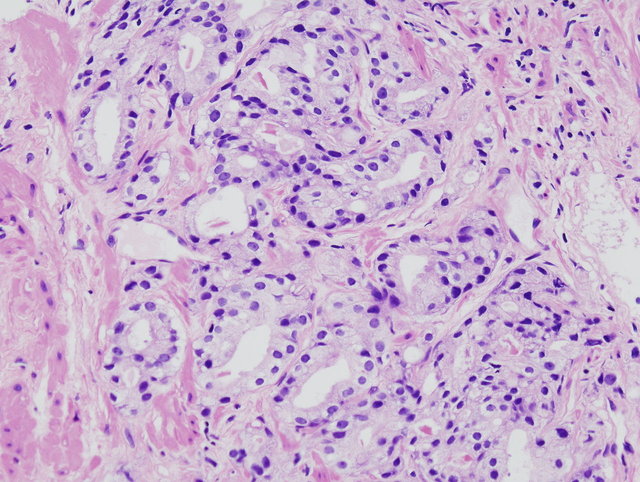

Histologische Sicherung der Diagnose mittels Stanzbiopsie (transrektal bzw. perineal), die feingewebliche Analyse ermöglicht zusätzlich ein Grading des Tumors (Gleason-Score)